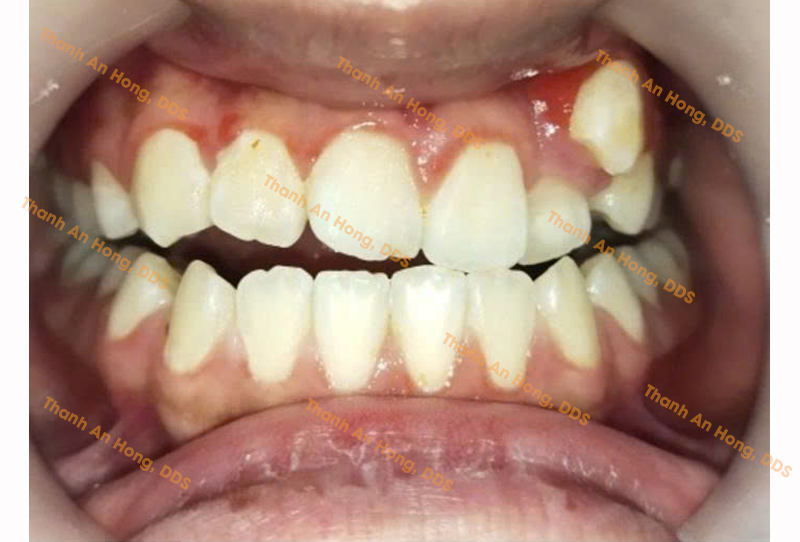

HÌNH ẢNH THỰC TẾ

Khay trong suốt chỉnh lệch đường giữa với toàn hàm là răng sứ